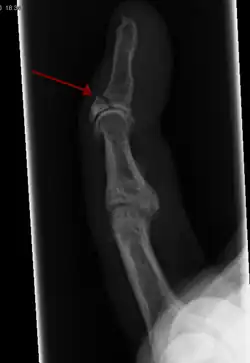

In the fingertip. More images

Linear fracture Parallel to the bone's long axis